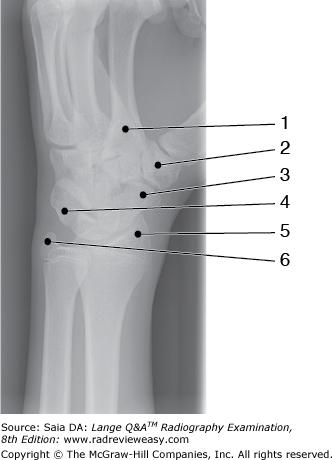

In Figure 2–29, which of the following is represented by the number 7?

A Medial border

B Lateral border

C Inferior angle

D Superior angle

-Figure 2–29 depicts a posterior view of the right scapula and its articulation with the humerus (number 4). The scapula presents two borders—the lateral or axillary border (number 7) and the medial or vertebral border (number 9). It also presents three angles—the inferior angle (number 8), the superior angle (number 12), and the lateral angle (number 6). The processes of the scapula are the coracoid (number 2), the acromion (number 3), and the scapular spine (number 13). The scapula has a (supra) scapular notch (number 1), a supraspinatus fossa (number 11), and an infraspinatus fossa (number 10). Number 5 identifies the glenoid fossa—the articular surface for the humeral head, forming the glenohumeral articulation.